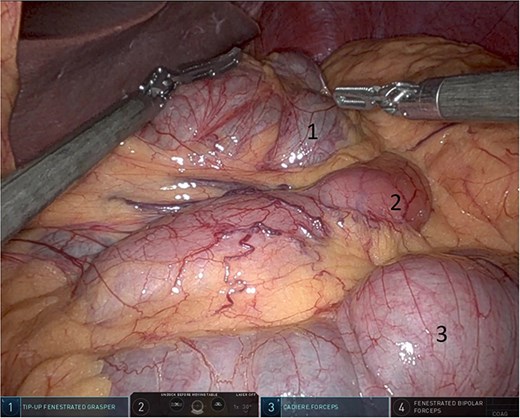

Upon entering the abdominal cavity, dilated bowel loops were observed (Fig. 2), and a significant portion of the colon was found herniated through the foramen of Winslow (Fig. 3). The herniated colon was covered by the pars flaccida (Fig. 4) (Video S1). Careful dissection was performed anterior to the hepatoduodenal ligament (Fig. 5). The gall bladder was retracted to the patient's right upper quadrant, which allowed for the retraction of the foramen of Winslow (Fig. 6) (Video S1). After carefully placing the tip of the instrument posterior to the portal vein and gently elevating it, the herniated colon was successfully reduced (Fig. 7) (Video S1).

Dissection anterior to the hepatoduodenal ligament (1: portal vein, 2: foramen of Winslow, 3:first part of the duodenum).